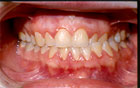

Fig.2 Ausencia de sectores posteriores Este estudio, nos ayuda a mantener el concepto de que el aumento de la carga articular por pérdida del soporte posterior (ausencia de molares) (Fig. 2), aumenta los signos y síntomas en los desórdenes craneomandibulares, incluyendo cambios estructurales óseos.

La mordida abierta anterior esquelética (Fig. 3), las sobremordidas horizontales de más de 6mm. (Fig. 4), una distancia mayor de 4mm. desde relación céntrica a máxima intercuspidación, mordida cruzada unilateral (Fig. 5 y 6) y ausencia de sectores posteriores de 5 ó más piezas, han sido los factores oclusales que se han asociado con grupos de diagnóstico específicos en disfunción de la ATM.